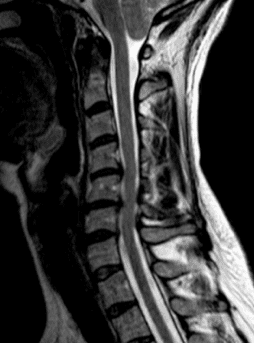

- Estenose do canal vertebral cervical. Neste tipo de afecção, o estreitamento ocorre na parte da coluna vertebral que corresponde à altura do pescoço.

- Ressonância Magnética (RM)